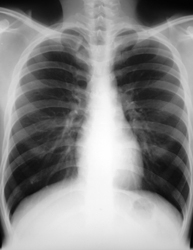

La radiographie thoracique montre le cœur, les poumons, les vaisseaux sanguins et les os. La radiographie consiste à projeter des rayons X à travers le corps pour créer des images sur une plaque de capture numérique. La quantité de radiation absorbée varie selon les parties du corps. Celles qui absorbent la plus grande quantité de radiation, comme les os, apparaissent en blanc sur la radiographie. Les parties qui absorbent une quantité plus faible de radiation (p. ex. le cœur) apparaissent en diverses teintes de gris. Les régions contenant de l’air, comme les poumons, apparaissent en noir. Les images radiographiques permettent de déceler une hypertrophie cardiaque (augmentation du volume du cœur) et la présence d’un œdème pulmonaire (liquide dans les poumons) – des symptômes associés à l’insuffisance cardiaque. Il faut souvent des images plus détaillées pour confirmer les anomalies perçues à la radiographie thoracique.